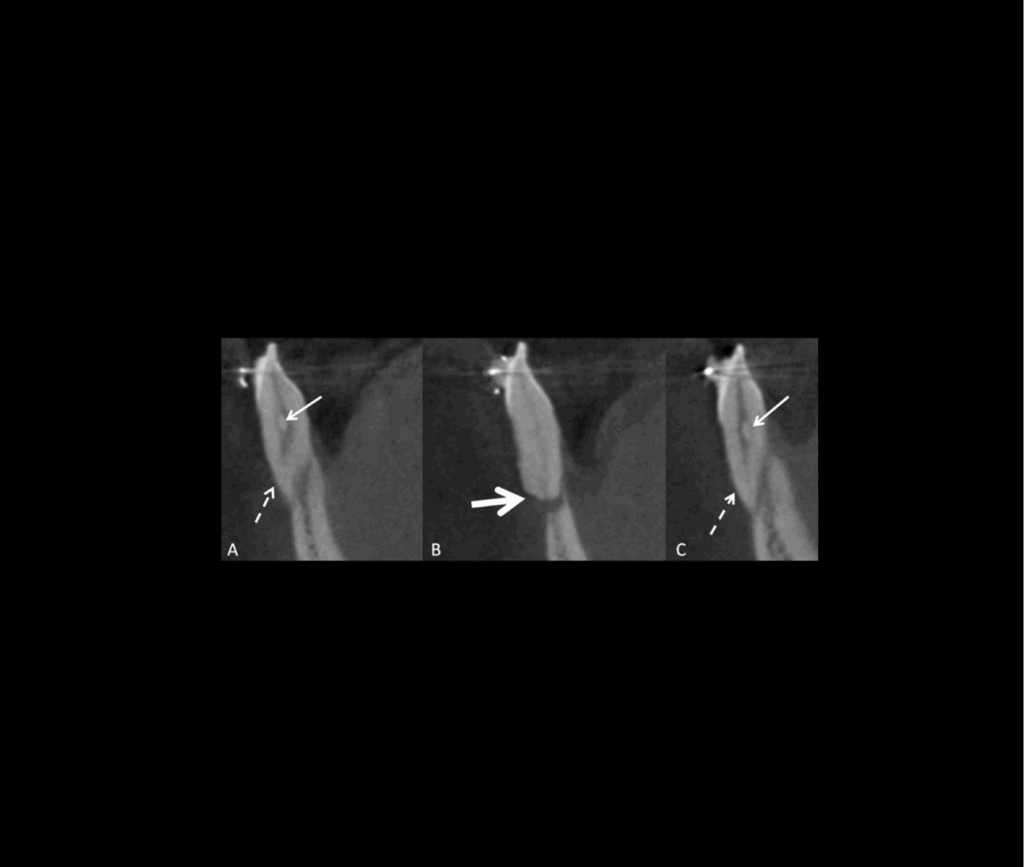

Revue illustrée des principales indications de CBCT en orthodontie

Revue illustrée des principales indications de CBCT en orthodontie Cet article examine les indications principales de l’utilisation de la tomographie volumique à faisceau conique (CBCT) en orthodontie, notamment pour les anomalies dentaires, les canines incluses, les dents surnuméraires, les troubles de l’éruption, et les résorptions radiculaires externes. Chaque utilisation du CBCT doit être justifiée individuellement pour […]